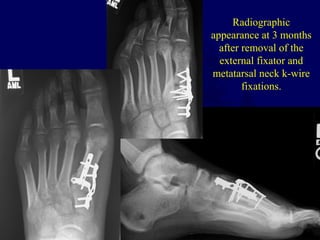

Radiographic

appearance at 3 months

after removal of the

external fixator and

metatarsal neck k-wire

fixations.